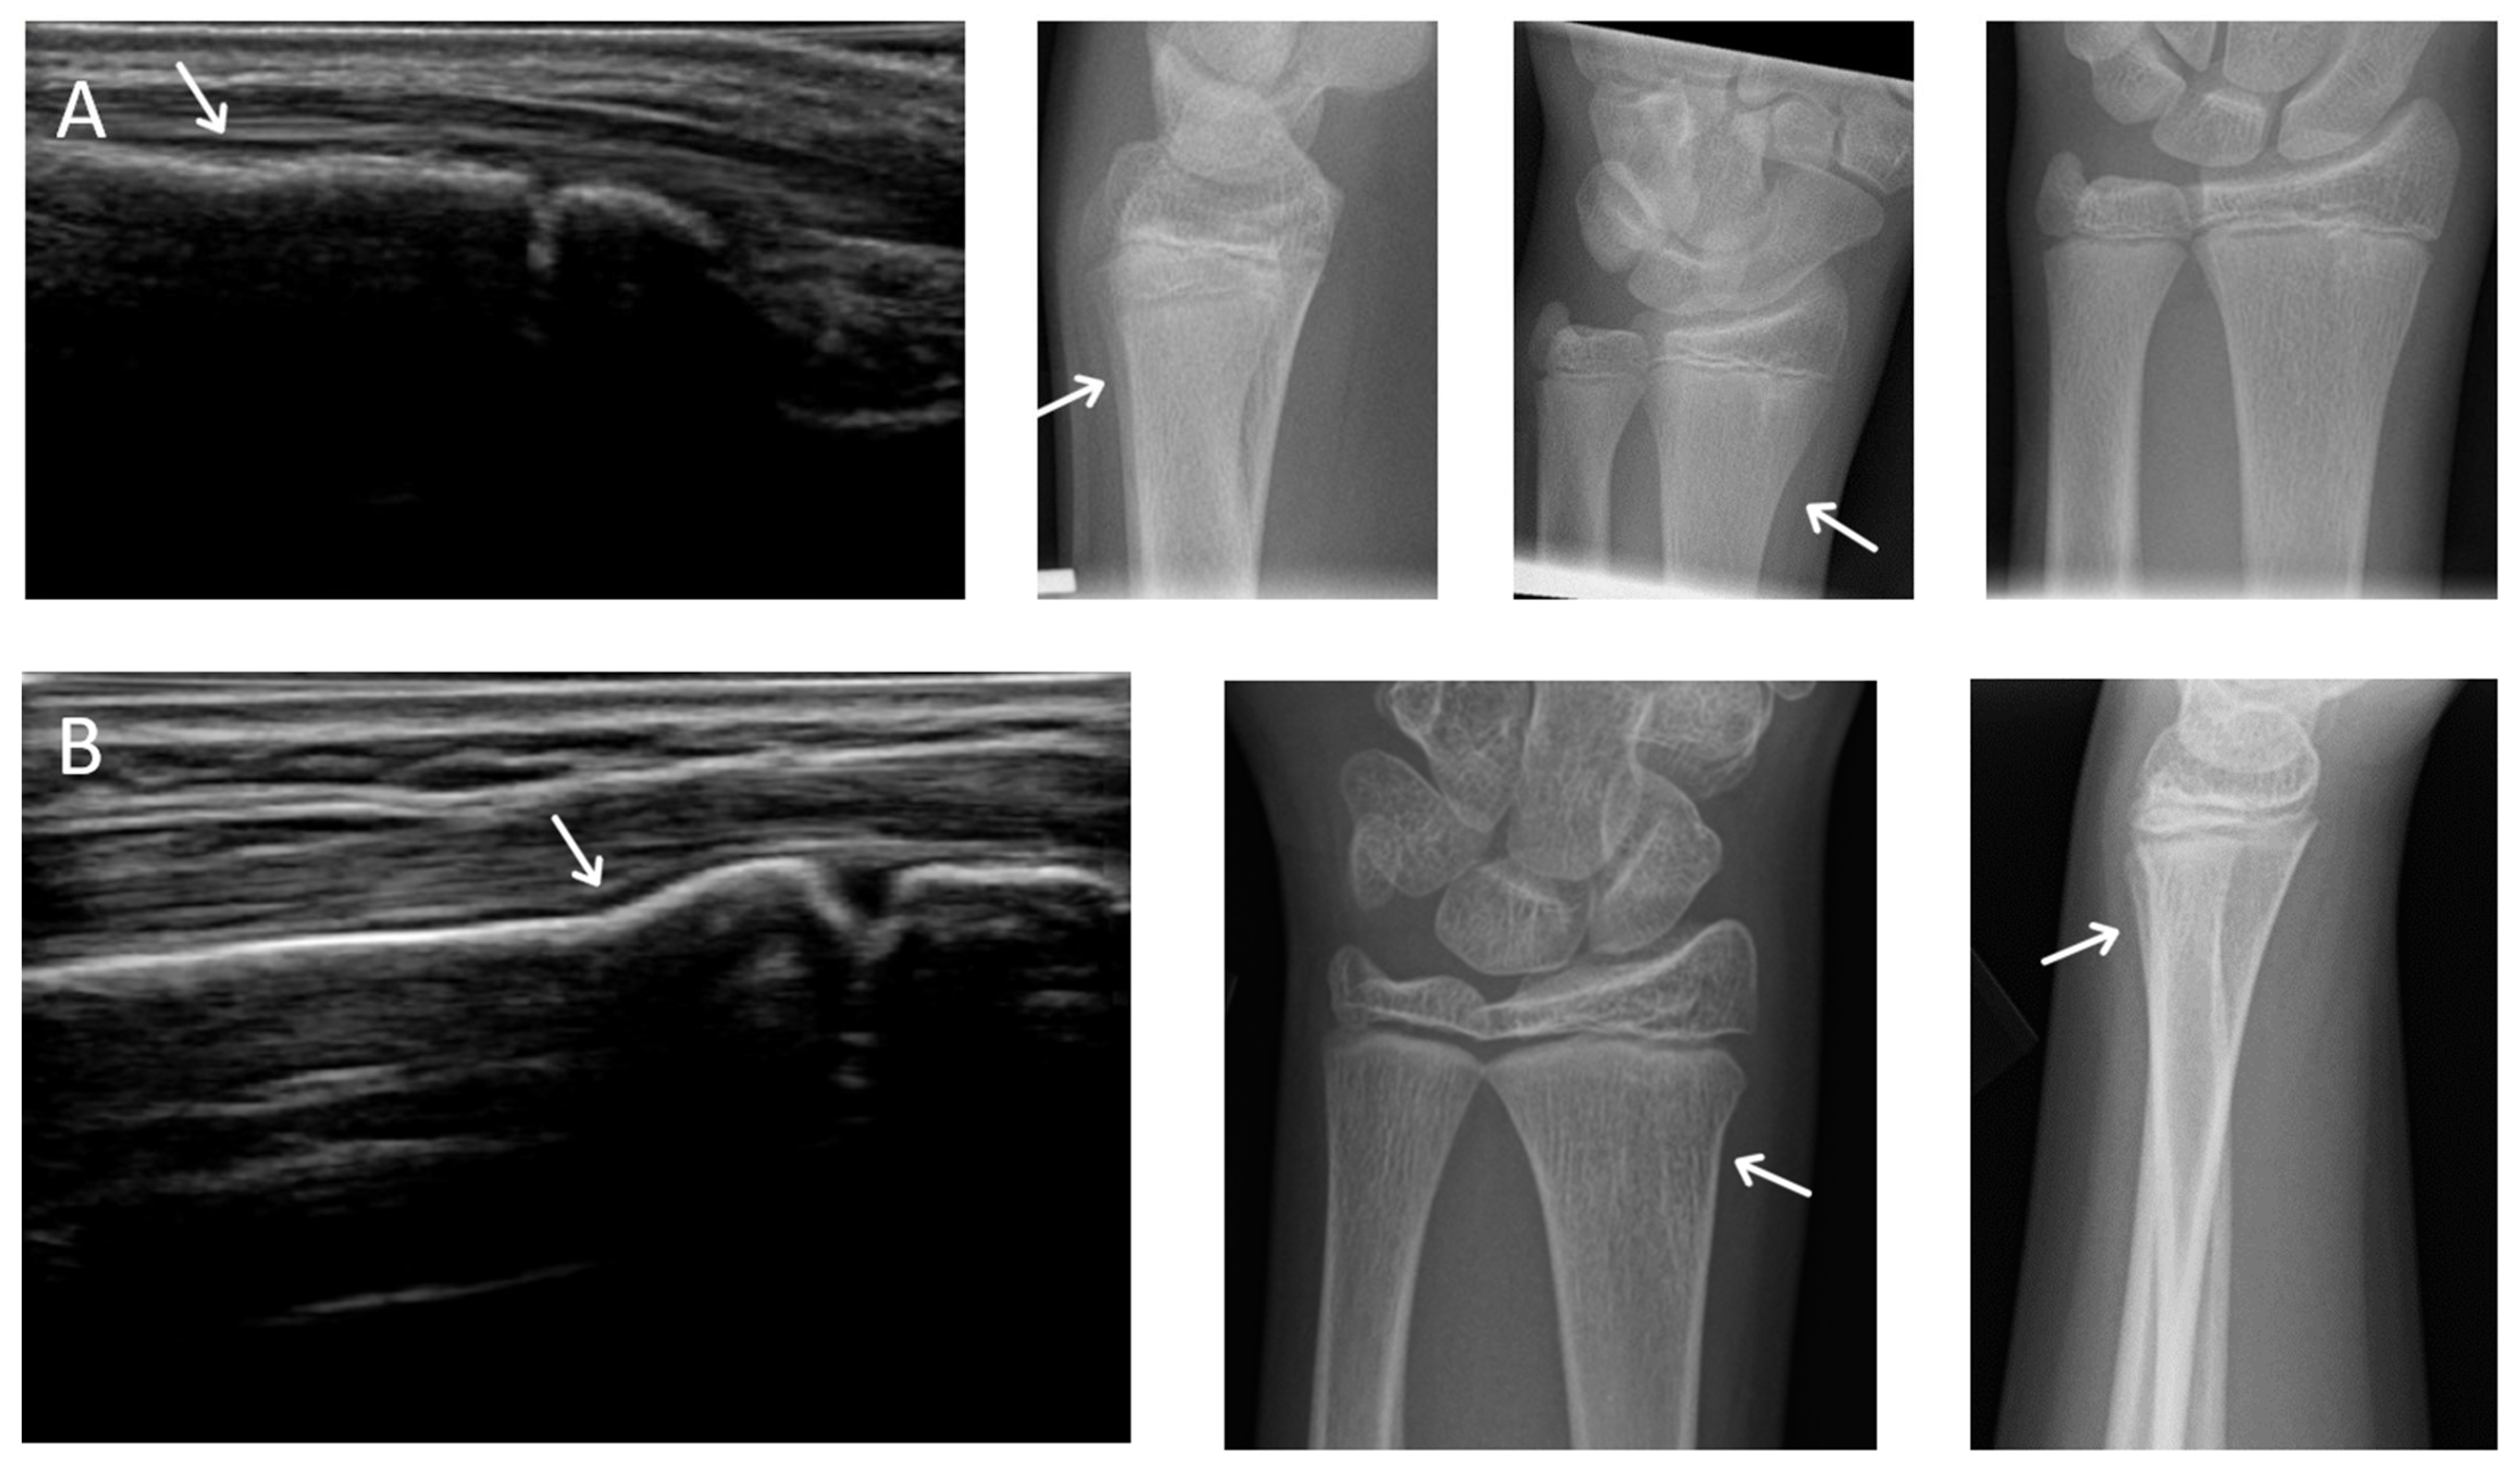

There were 2 possible radiographic false negatives out of 10 negative radiographs, as the US revealed subtle cortical irregularities that could represent undisplaced fractures. Retrospective review of two X-rays in light of ultrasound findings showed subtle cortical contour irregularities that might have represented the fractures identified on US (Figure 3). Previous studies had also reported the possibility that ultrasound may identify subtle fractures not seen on radiographs [7]. The clinical significance of these possible undisplaced fractures is unknown. Future study could potentially perform limited MRI in this small subset of patients with discrepant ultrasound/X-ray findings to clarify vs. an external gold standard.

Figure 1. Possible missed fractures. (A,B) are dorsal longitudinal views of the distal radius of two possible X-ray false negatives. Note the excess angulation of the distal radius may represent torus fractures. The possible defect is observable on X-ray.